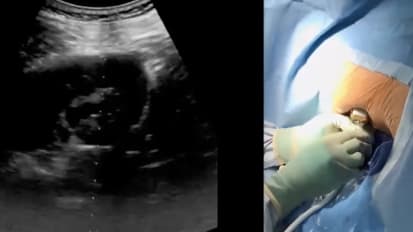

So I'm gonna talk a little bit about mhm the equipment itself and what's involved in doing Ah, MEP, I think once you're armed with with the tools for access which Doctor, sir gave a really nice talk on the shifting towards ultrasound, I'm going to just touch on the tools and how you can take advantage of them. And what would the potential benefits be over another system? So the MIPS set, which is a minimally invasive PCL, um, this is a picture of the entire set. It's nice because it's a modular, reusable system. Eso everything that you need, you know, for the actual procedure is here now. Obviously, there are some additional equipment items you need for getting access for performing with a trip. See, but in general, the equipment for dilation navigating the kidney. There's even a grasshopper that comes with the set for stone removal. Um, pretty much the majority. The equipment that you need isn't contained in this set, and it's reusable. That potentially translates into cost effectiveness. A Z you are cutting down on your needs for disposable items on a canvas illit ated a to Bliss PCL or even an outpatient PCL. because of the size of the track in the United States, there's three main size sets designated small, medium and large or a myth s myth em up myth l that really refers to the size of the Nef ra scope. Uh, the camera. So we primarily is the myth M set, which is a 12 French scope, and it comes with three different chief sizes that range from a 15 or 16 French, 17.5 French in a 22 French. You can see those laid out here. Each sheath comes into lengths. There's a regular length on, then a length designated with an S for supine, which is to facilitate. If you're doing the case in a prone versus a supine position, it's slightly longer to account for the increase skin to stone distance for lower poll in the supine position. So once you've picked a size, the the equipment that you need is shown here. All you really need is a single step violator you can see in the video that's me putting the dilation operator through the operating chief. Eso you need your sheath, you need your dilator. You need the net for a scope and then possibly a sealant applicator to close the tract. When you're all done and again, it's a single step dilation, which will come back to so simplifies the process. So some key features of the MIPS set obviously it's size is very advantageous. Um, compared to Standard PCL, which often are either 24 or 30 French dilation tracks, you could make a much smaller tracked here. The single step dilation we talked about. One advantage of this set is that it's an open system design. What I mean by that is the sheath itself and the telescope are not locked together, so you can see in this picture Bye bye. Maintaining freedom of movement of the camera, um, independent from the outer sheath, it maintains an open channel for outflow around the Net. Frisco. By doing that, you could really maintain a lower pressure state in the kidney because you're not at risk for blocking the outflow, which could lead to increased pressures inside the kidney. It also facilitates stone extraction, um, using the vacuum effect which will touch on in a minute. Obviously, this system allows you to close the track after with sealant. If you want. And then there's a large angle of view relative to the scope, and that's because the NYT FRA scope itself. It is very small compared to the diameter of your access chief and the regulation on the camera. So it translates into a very good visibility inside. So the vacuum effect, I think this is one of the main advantages of the MEP is it facilitates fast removal of stones of both dust and also small particles. The idea is the in flow through the Net Frisco has shown by this red current creates an eddy current approximately 1 to 2 centimeters in front of the tip of the camera, and then the draining fluid, which comes outside the sheath because of the physics of that interaction, creates an eddy current right in front of the camera, which you can use to trap stones. And by withdrawing the Net, Frisco pure actually withdrawing larger stone fragments in this eddy current, and then the continuous flow promotes smaller dust and fragments toe also drain on their own at the same time. An advantage of this is it could potentially is faster, and you don't need to use disposable retrieval devices such as baskets and grass spurs. The video from Dr Sir that highlights this effect. You can see here there's a never a scope is inserted. You can see the continuous drainage of fluid around the sheath. And then, as you bring the scope back, you can see the stone pieces air coming out, landing on that gauze pad beneath the camera. There, you can see on the right. Uh, there's a stone that's being trapped right there, and it's held about one centimeter in front of the scope all the way as it's being withdrawn. And some of the subtle tips are as you're withdrawing the stone, you want to tip your risk so that you can maintain that that vacuum effect all the way to the end of the sheath and you can see in a pretty short time he's already pulled out. There's at least eight large stone fragments visible on that cause, so if done right, it's a very fast and efficient step. So I'm going to just go through quickly the steps of the procedure overall and and, uh, and then show you sort of one option for technique and how to use the system So the first step, obviously, is Thio, get your literal access on this Could be done depending on how your set up is. I personally do assist Oscar P, um, place. So you read your catheter, but you can also do a retrograde eureka. Rosco p, this is a picture showing the table set up so you can see, in my case, I've selected the MIT M set. So, really, all I have is my sheath, my introduction, my dilating operator on my net for a scope. And then I have a few other things that come with your and my access needles over here. That's the methylene blue. Have a one suitor for the end of the case, So I I do prone positioning. So after we've placed a urethral catheter, we then, uh, with the patient and prone position and you can see have a set up similar to Dr Sirs illustration. We have the C arm up here, the compliment access, and then the visualization monitors. And at the foot of the bed is the ultrasound monitor. Here. This is just shown with the lights off. You can see there's a nice view, so step two, obviously obtaining access, and this could be through a variety of technique on. And once you, the key is obviously getting access with. Here's a flash of urine. In this case, we've used methylene blue, Um, and then you want to pass your wire either into the kidney or ideally down the ureter into the bladder. Thing is the single step dilation, which is, um, one of the hallmarks is, once you have your wire, you twist your operator over the wire in a slow fashion. You can use Flora's to be to guide it, and when you're in, you can see there's a second port that were alluding to here and that will drain urine so you know the operators in the right place. When you see your coming out, you then pass the second wire through this channel. Once you've done that, you actually withdraw the dilator off of the two wires and reinsert it just over one of the wires. That so that you can maintain a safety wire outside of the tracked. And here you can see we're advancing the sheath over the violating operator. You can see the sheath there once it's confirmed inside the kidney Then you can remove the the working wire and the Interop traitor, and you have just a working sheath with a wire safety wire outside of that system. If you're having difficulty, there's other maneuvers you can use. You can possibly use a A 10 French or 8 10 French dilator to pre dilate the tract prior to passing the dilator, Um, or even a balloon. Um, the next step is treating the stone, so this is using either laser or a with a trip to of your choice. Commonly, I think people use some form of laser. Uh, nowadays, I do think that the Moses or a dusting laser, or even a few Liam any of these higher energy laser systems that enable dusting of the stones, um, potentially will lead to faster drainage. Due to the vacuum effect of the myth, you can both extract the stones as we've seen, and also drain all the dusting in the small stone fragments and then at the end, um, either leaving a frost me tube. Although this system, to be honest, really is, is geared for leaving an internalized, you literal stent, potentially even going totally to bliss in our practice, we leave a stent with an external, uh, tether. So we place the stent and then leave the string externalized thru are tracked. This facilitates easier removal. 3 to 5 days later, the patient comes into the office. One of the nurses just removes the stent by pulling the string. It also saves the patient having under grossest Oscar P, which many men are particularly excited about on you can see here that there's just a Band Aid left behind.